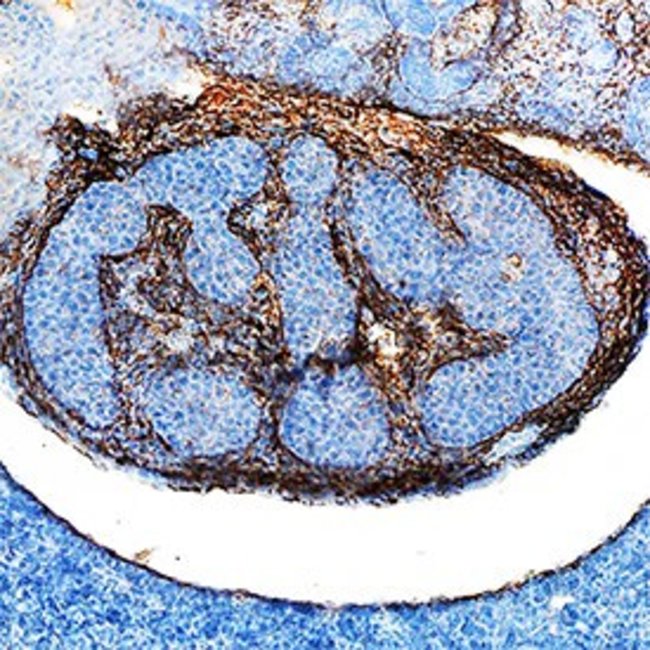

Invitrogen™ TGFBI Polyclonal Antibody

Supplier: Invitrogen™ PA547346

This gene encodes an RGD-containing protein that binds to type I, II and IV collagens. The RGD motif is found in many extracellular matrix proteins modulating cell adhesion and serves as a ligand recognition sequence for several integrins. This protein plays a role in cell-collagen interactions and may be involved in endochondrial bone formation in cartilage. The protein is induced by transforming growth factor-beta and acts to inhibit cell adhesion. Mutations in this gene are associated with multiple types of corneal dystrophy.

| ELISA, Immunohistochemistry (Frozen), Western Blot | |

| Mouse myeloma cell line NS0-derived recombinant mouse beta IG-H3 Gly24-His683. | |